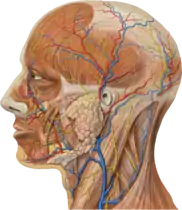

Human Physiology explains, system by system, the workings of your body. It is intended as an understandable undergraduate-level guide to how the body systems function at a cellular level and how they work together to maintain a favorable environment for your cells. You and your class are invited to use and improve this book!